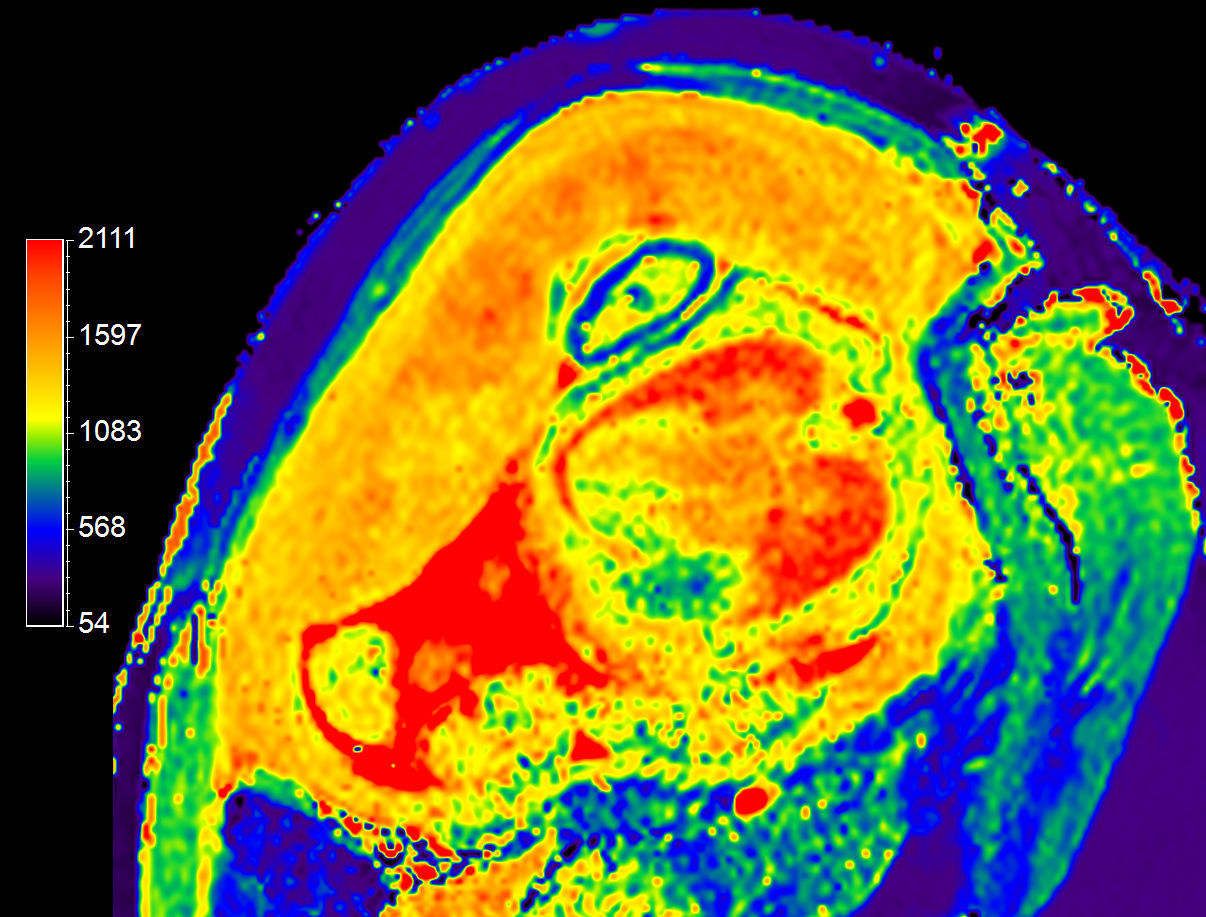

T1 Map